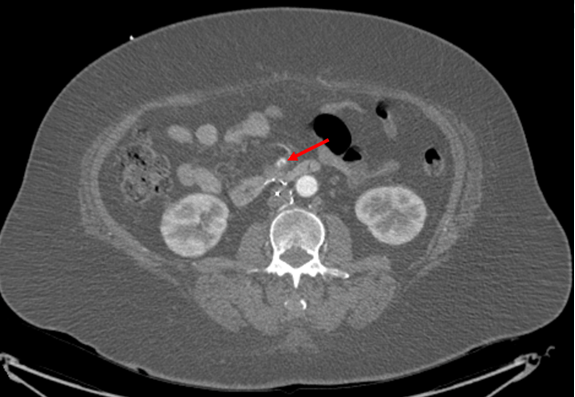

Rate control was achieved with diltiazem infusion and anticoagulation with intravenous heparin was initiated. Echocardiogram showed a left atrial mass adjacent to the interatrial septum suspicious for atrial myxoma (Figure 1). Computed tomography scan showed a left atrial filling defect that enhanced with contrast and measured 4.5x3.3x4.4 cm (Figure 2) as well as a filling defect in the superior mesenteric artery (Figure 3). Lower extremity angiogram demonstrated abrupt cessation of flow consistent with an embolus to the right popliteal artery (Figure 4) and a patent left popliteal artery. Right popliteal arterial thrombectomy was performed. The patient then underwent excision of the left atrial mass. Maze procedure and left atrial appendage ligation. The examination of excised mass revealed an organized thrombus (Figure 5). The postoperative course was uneventful and the patient was discharged on warfarin and metoprolol.

Figure 3: Computed tomography scan abdomen demonstrating filling defect in the superior mesenteric artery (arrow).